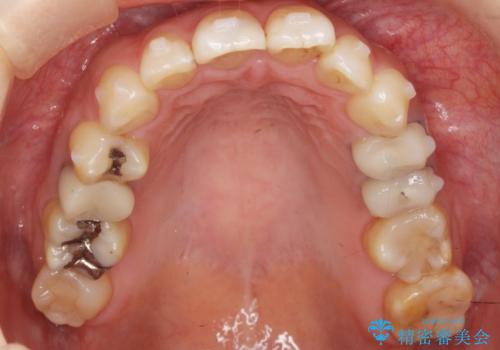

ご希望のマウスピース矯正で歯並びが綺麗になり、大変喜んで頂けました。

治療後には笑うと見えて気になっていた銀歯も白くなり、より一層素敵な笑顔を見せて下さいました。

ホワイトニング予定のため、セラミッククラウンの色は隣在歯よりやや白めにオーダーしました。

クラウンの種類:オールセラミッククラウン エコノミー(e-max press Cr)

インレーの種類:e-max press セラミックインレー